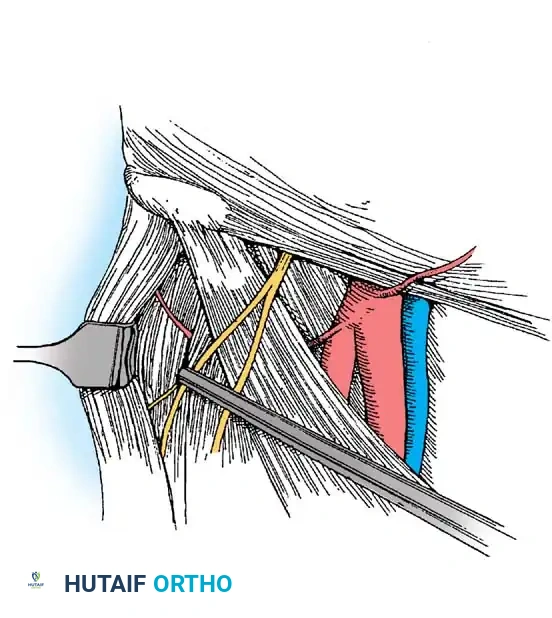

Management of Labral Injuries (Technique 48-40)

Labral injuries most commonly result from traumatic hyperextension and external rotation of the hip, or repetitive microtrauma secondary to FAI. Lesions most frequently involve the anterior and anterosuperior margins of the labrum.

Tears are broadly divided into:

* Type I: Peripheral capsulolabral detachment (often amenable to repair).

* Type II: Intrasubstance tears or complex maceration (often requiring débridement or reconstruction).

Because the blood supply to the labrum is located peripherally (similar to the meniscus of the knee), peripheral detachments have excellent healing potential when anatomically repaired.

Labral Repair Technique

- Positioning for Repair: Place the patient in the modified supine position: 10 degrees of flexion, 15 degrees of internal rotation, 10 degrees of lateral tilt, and neutral abduction.

- Distraction Protocol: Using an extra-wide perineal post, place the leg first in abduction and apply traction to break the vacuum seal. Then, adduct the leg over the post to force the femoral head laterally. Apply straight, in-line traction until 8 to 10 mm of joint space is achieved (typically requiring 25 to 50 lbs of force). Apply gentle countertraction to the contralateral limb.

- Accessory Portals: Three portals are typically required for complex arthroscopic labral repair: the anterolateral, the anterior, and a Distal Lateral Accessory (DLA) portal. The DLA portal provides the optimal trajectory for drilling suture anchors into the acetabular rim without penetrating the articular cartilage.

- Bed Preparation: Use interchangeable, flexible cannulas and curved shaver blades to lightly decorticate the acetabular rim, exposing a bleeding bone bed to stimulate a healing response.

- Anchor Placement: Drill and place knotless or knotted suture anchors along the acetabular rim. Pass the sutures around or through the labral tissue using specialized suture-passing devices, and tie them down to restore the anatomical suction seal of the hip joint.